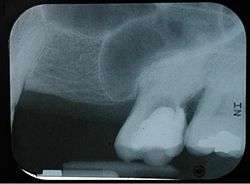

Projecting into the floor of the antrum are several conical processes, corresponding to the roots of the first and second maxillary molar teeth; in some cases the floor can be perforated by the apices of the teeth.

With age, the enlarging maxillary sinus may even begin to surround the roots of the maxillary posterior teeth and extend its margins into the body of the zygomatic bone. If the maxillary posterior teeth are lost, the maxillary sinus may expand even more, thinning the bony floor of the alveolar process so that only a thin shell of bone is present.[3]